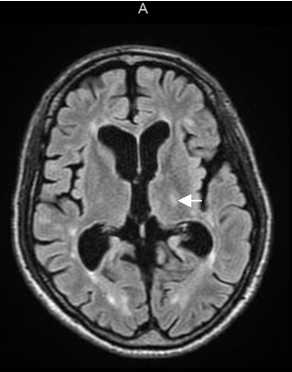

Brain MRI lesions were found in periventricular, subcortical, thalamus and brainstem. Lesion location seemed to play an important role in the presence of pain. Moderate to severe pain was found in 92.3% of the patients that had a lesions in the thalamus and in 86% of the patient's with brainstem lesions (Figure 1 and 2).

Figure 1 Brain MRI flair sequence which shows a left hypenintense thalamic lesion (arrow).

We found a significantly higher proportion of thalamus and brainstem lesions in males (p=0.018, and p=0.009 respectively). Spinal, thalamus, and brainstem lesions combined showed also a higher proportion for males than females (p=0.043). Brainstem lesions were present in 29 patients, of which 86% were complaining of moderate to severe pain. Spine MRI was available for 84 patients, and 61% of patients with lesions in the spinal cord reported moderate to severe pain.

Of the patients with lesions limited to the subcortical and periventricular regions, 69% reported having moderate to severe pain. This was significantly different from patients who had thalamic or brainstem lesions, where 85% or more of them reported similar symptoms.